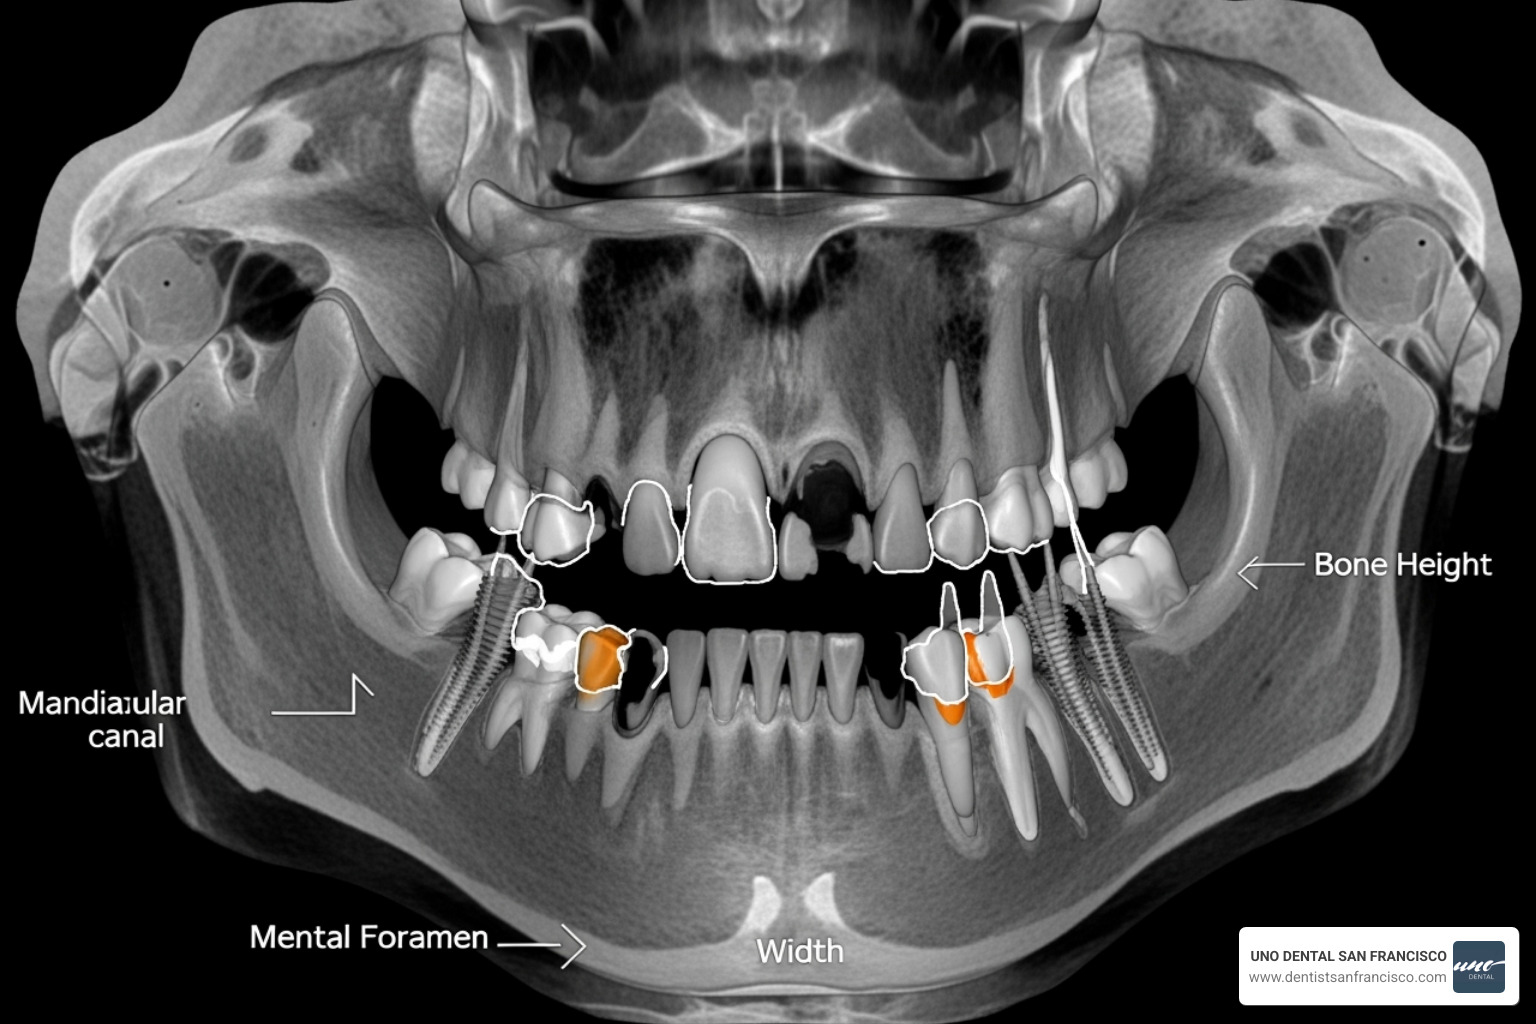

At UNO DENTAL, we begin with a comprehensive diagnosis, including a 3D CBCT scan. This provides a precise view of your jawbone, nerves, and sinuses, allowing us to plan your treatment with accuracy. This diagnostic step ensures we can provide a realistic and transparent cost estimate with no surprises. To learn more about our services, please visit our Dental Procedures List.

Advanced technology also influences the cost of full mouth dental implants San Francisco. We use cutting-edge tools like 3D imaging and guided surgery systems. Cone Beam CT scans ($100 - $1,000) allow for precise implant placement, avoiding nerves and maximizing bone integration. This investment in expertise and technology ensures your implants serve you well for decades.